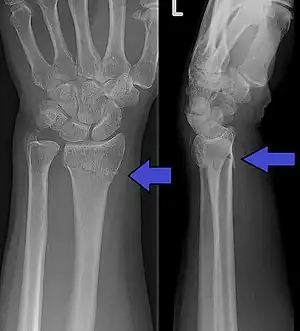

Bilateral Colles fractures/frontal

Bilateral Colles fractures/lateral

The fracture is most commonly caused by people falling onto a hard surface and breaking their fall with outstretched hand (FOOSH)–falling with wrists flexed would lead to a Smith's fracture. Originally it was described in elderly and/or post-menopausal women. It usually occurs about three to five centimetres proximal to the radio-carpal joint with posterior and lateral displacement of the distal fragment resulting in the characteristic "dinner fork" or "bayonet" like deformity. Colles fracture is a common fracture in people with osteoporosis, second only to vertebral fractures.

The term Colles fracture is classically used to describe a fracture at the distal end of the radius, at its cortico-cancellous junction. However, the term now tends to be used loosely to describe any fracture of the distal radius, with or without involvement of the ulna, that has dorsal displacement of the fracture fragments. Colles himself described it as a fracture that “takes place at about an inch and a half (38mm) above the carpal extremity of the radius” and “the carpus and the base of metacarpus appears to be thrown backward”.[10] The fracture is sometimes referred to as a "dinner fork" or "bayonet" deformity due to the shape of the resultant forearm.